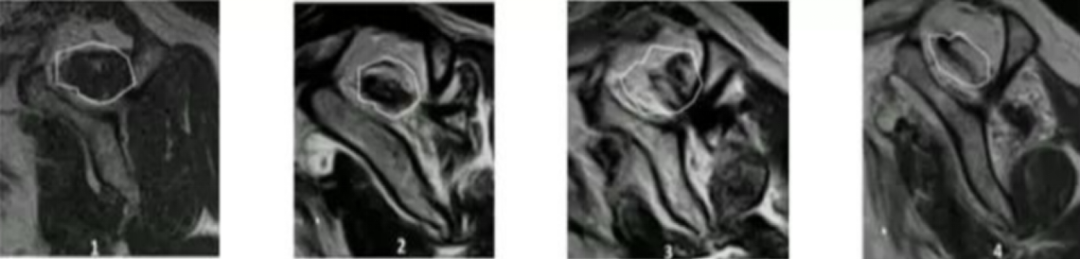

磁共振及磁共振关节造影:MRI是目前检查肩袖损伤最有效的影像学方法。MRI通过形态和信号的异常反应可显示肩袖损伤的各期表现。磁共振关节造影是在透视下经关节囊内注射含碘造影剂。由于关节囊的扩张,微小的肩袖撕裂在造影剂的衬托下显示得更为清楚,磁共振关节造影的准确率超过90%。